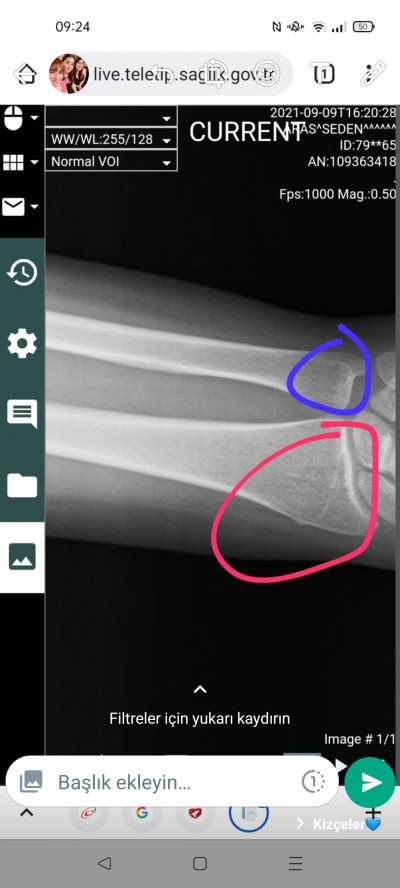

Ben geçen cuma düşüp bileğimi kırdım. Acildeki doktor bana kırmızı yerin kırıldığını söyledi ama mavi yer de agiriyo kırık olduğunu düşünüyorum ama emin değilim. Ama sadece kırmızı yere alçı koydular

İyiyim canım çok şükür. Ecem de iyi. Bilegim agiriyor hala 3 kırık varmıs doktor alciyi alırken söyledi. İlaç kulwlniyorum elimi sariyorum. Sen nasılsın Cem nasıl? Neden yeni hesap actin ben artık sürekli giremiyorum

Kırıkmış doktor alciyi çıkarırken söyledi